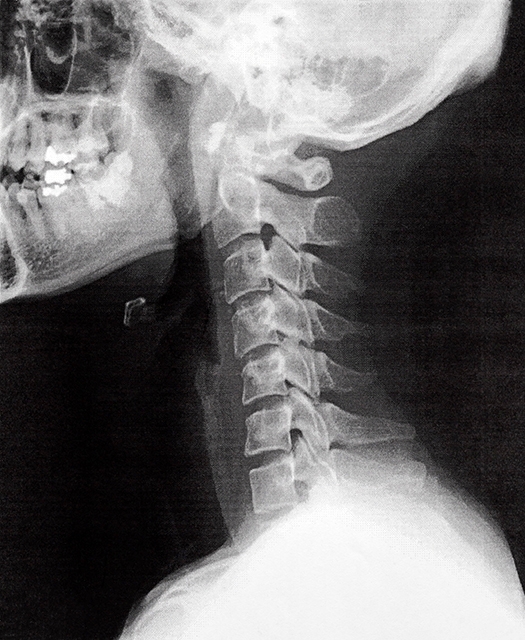

「むち打ち」とは、交通事故などで首が前後に大きくしなることで起こる頸部の損傷のことを指します。

特に追突事故で発生しやすく、レントゲン上で骨に異常がなかったり、見た目や早期に異常がなくても深部の組織にダメージを受けている可能性があり、靭帯・筋肉・神経などを痛めることで痛みや不調が生じます。

むち打ちは病院で診断を受ける場合、「頚椎捻挫」や「外傷性頚部症候群」とされます。